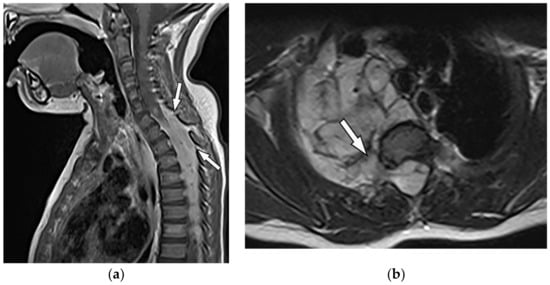

8.2. Tuberculosis Spondylodiskitis

Tuberculosis spondylodiskitis has a more gradual and chronic clinical course, which leads to multi-level involvement and paravertebral cold abscess formation with well-circumscribed thin wall. Subligamentous spread of infection to adjacent vertebral levels, relative preservation of intervertebral disk, and kyphotic angulation (gibbous deformity) are other imaging findings. CT scan is more sensitive in delineating calcification within paravertebral cold abscess, end plate erosion, and bony fragment visualization (Figure 13) [39,42].

Figure 13.

A 65-year-old man with fever, weight loss, and night sweeting. The non-contrast-enhanced CT (bone window) in axial plane (a) shows paraspinal soft tissue mass with erosion of right lateral aspect of adjacent vertebral body. Sagittal T2W image of another patient with the same pathology (b) shows hypersignal intensity within T8-T9 vertebral bodies with also intervertebral disc destruction and narrowing of spinal canal pushing the spinal cord posteriorly. Axial T1WFS + C (c) identified the enhancing paraspinal mass with peripheral rim enhancement (arrow) in its left posteromedial side, which is suggestive of abscess formation. Culture of aspirated pus under guide of CT was compatible with tuberculosis infection.